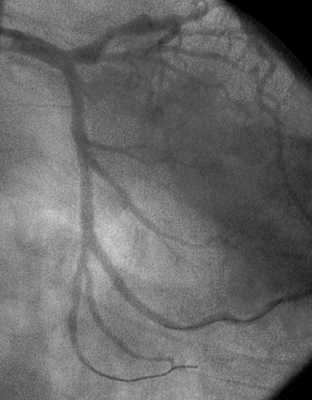

Поздний тромбоз был выявлен у 1 (0, 3%) пациентки. Через 46 месяцев после провизионального Т-стентирования ствола ЛКА с переходом на ПМЖВ (в ПМЖВ имплантировано 2 стента “Cypher”) у больной развилась клиника ОИМ передней локализации. При контрольной КГ был выявлен тромбоз стента в с/3 ПМЖВ (область бифуркации ствол-ОВ-ПМЖВ без значимых изменений). Больной выполнена реканализация, ТЛБАП и стентирование ПМЖВ с хорошим клиническим результатом. Пример бифуркационного стентирования приведены на рис. 3.

Чаще всего выполнялось стентирование бифуркационных поражений передней межжелудочковой ветви (ПМЖВ) и диагональной ветви (ДВ) левой коронарной артерии - всего 256 (70, 7%) из 362 случаев. Огибающая артерия (ОА) и ее ветви (ВТК, ЗБВ, ЗМЖВ) были стентированы в 42 (11, 6%) случаях, правая коронарная артерия (ПКА) и ее ветви (ЗБВ, ЗМЖВ, ВОК) - в 31 (8, 6%). Также нами было проведено стентирование 33 (9, 1%) бифуркационных поражений, локализованных в стволе ЛКА (в сочетании с устьевыми поражениями ПМЖВ, ОВ или а. intermedia). Согласно классификации Medina, 284 (78, 5%) бифуркационных сужений из 362 являлись истинными.